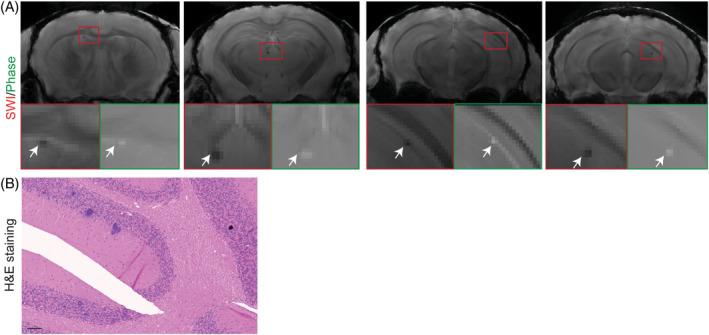

Abnormal alpha-synuclein (αSyn) and iron accumulation in the brain play an important role in Parkinson's disease (PD). Herein, we aim to visualize αSyn inclusions and iron deposition in the brains of M83 (A53T) mouse models of PD in vivo. The fluorescent pyrimidoindole derivative THK-565 probe was characterized by means of recombinant fibrils and brains from 10- to 11-month-old M83 mice. Concurrent wide-field fluorescence and volumetric multispectral optoacoustic tomography (vMSOT) imaging were subsequently performed in vivo. Structural and susceptibility weighted imaging (SWI) magnetic resonance imaging (MRI) at 9.4 T as well as scanning transmission x-ray microscopy (STXM) were performed to characterize the iron deposits in the perfused brains. Immunofluorescence and Prussian blue staining were further performed on brain slices to validate the detection of αSyn inclusions and iron deposition. THK-565 showed increased fluorescence upon binding to recombinant αSyn fibrils and αSyn inclusions in post-mortem brain slices from patients with PD and M83 mice. Administration of THK-565 in M83 mice showed higher cerebral retention at 20 and 40 min post-intravenous injection by wide-field fluorescence compared to nontransgenic littermate mice, in congruence with the vMSOT findings. SWI/phase images and Prussian blue indicated the accumulation of iron deposits in the brains of M83 mice, presumably in the Fe form, as evinced by the STXM results. In conclusion, we demonstrated in vivo mapping of αSyn by means of noninvasive epifluorescence and vMSOT imaging and validated the results by targeting the THK-565 label and SWI/STXM identification of iron deposits in M83 mouse brains ex vivo.